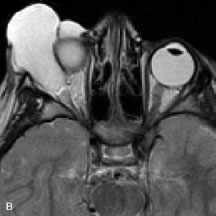

INTRAOCULAR TUMORS

On MRI, uveal melanomas have a typical appearance that helps to differentiate them from other primary and secondary intraocular tumors as well as choroidal detachments. Pigmented melanomas are hyperintense on Tl-weighted images, hypointense on T2-weighted studies, and hyperintense on proton density–weighted examinations (Fig. 24).30,31,50,80–82 These signal characteristics have been attributed to the paramagnetic properties of melanin because of stable free radicals that shorten the T1 and T2 relaxation times. Moderate enhancement is seen on postgadolinium T2-weighted images. Gadolinium-enhanced T1-weighted images are particularly sensitive in detecting choroidal melanomas.83 MRI may be less sensitive in detecting extrascleral extension of tumor than echography performed by an experienced ultrasonographer.84

Fig. 24. A. T1- and (B) T2-weighted MR scans demonstrate a small nodular intraocular mass (arrows) that is very hyperintense on the T1-weighted scan and hypointense on the T2-weighted image. This signal intensity pattern is due to the presence of free radicals within melanin granules. C and D. Postcontrast fat-suppressed T1-weighted scans demonstrate homogeneous intense enhancement of the lesion and no evidence of seleral penetration or optic nerve invasion.